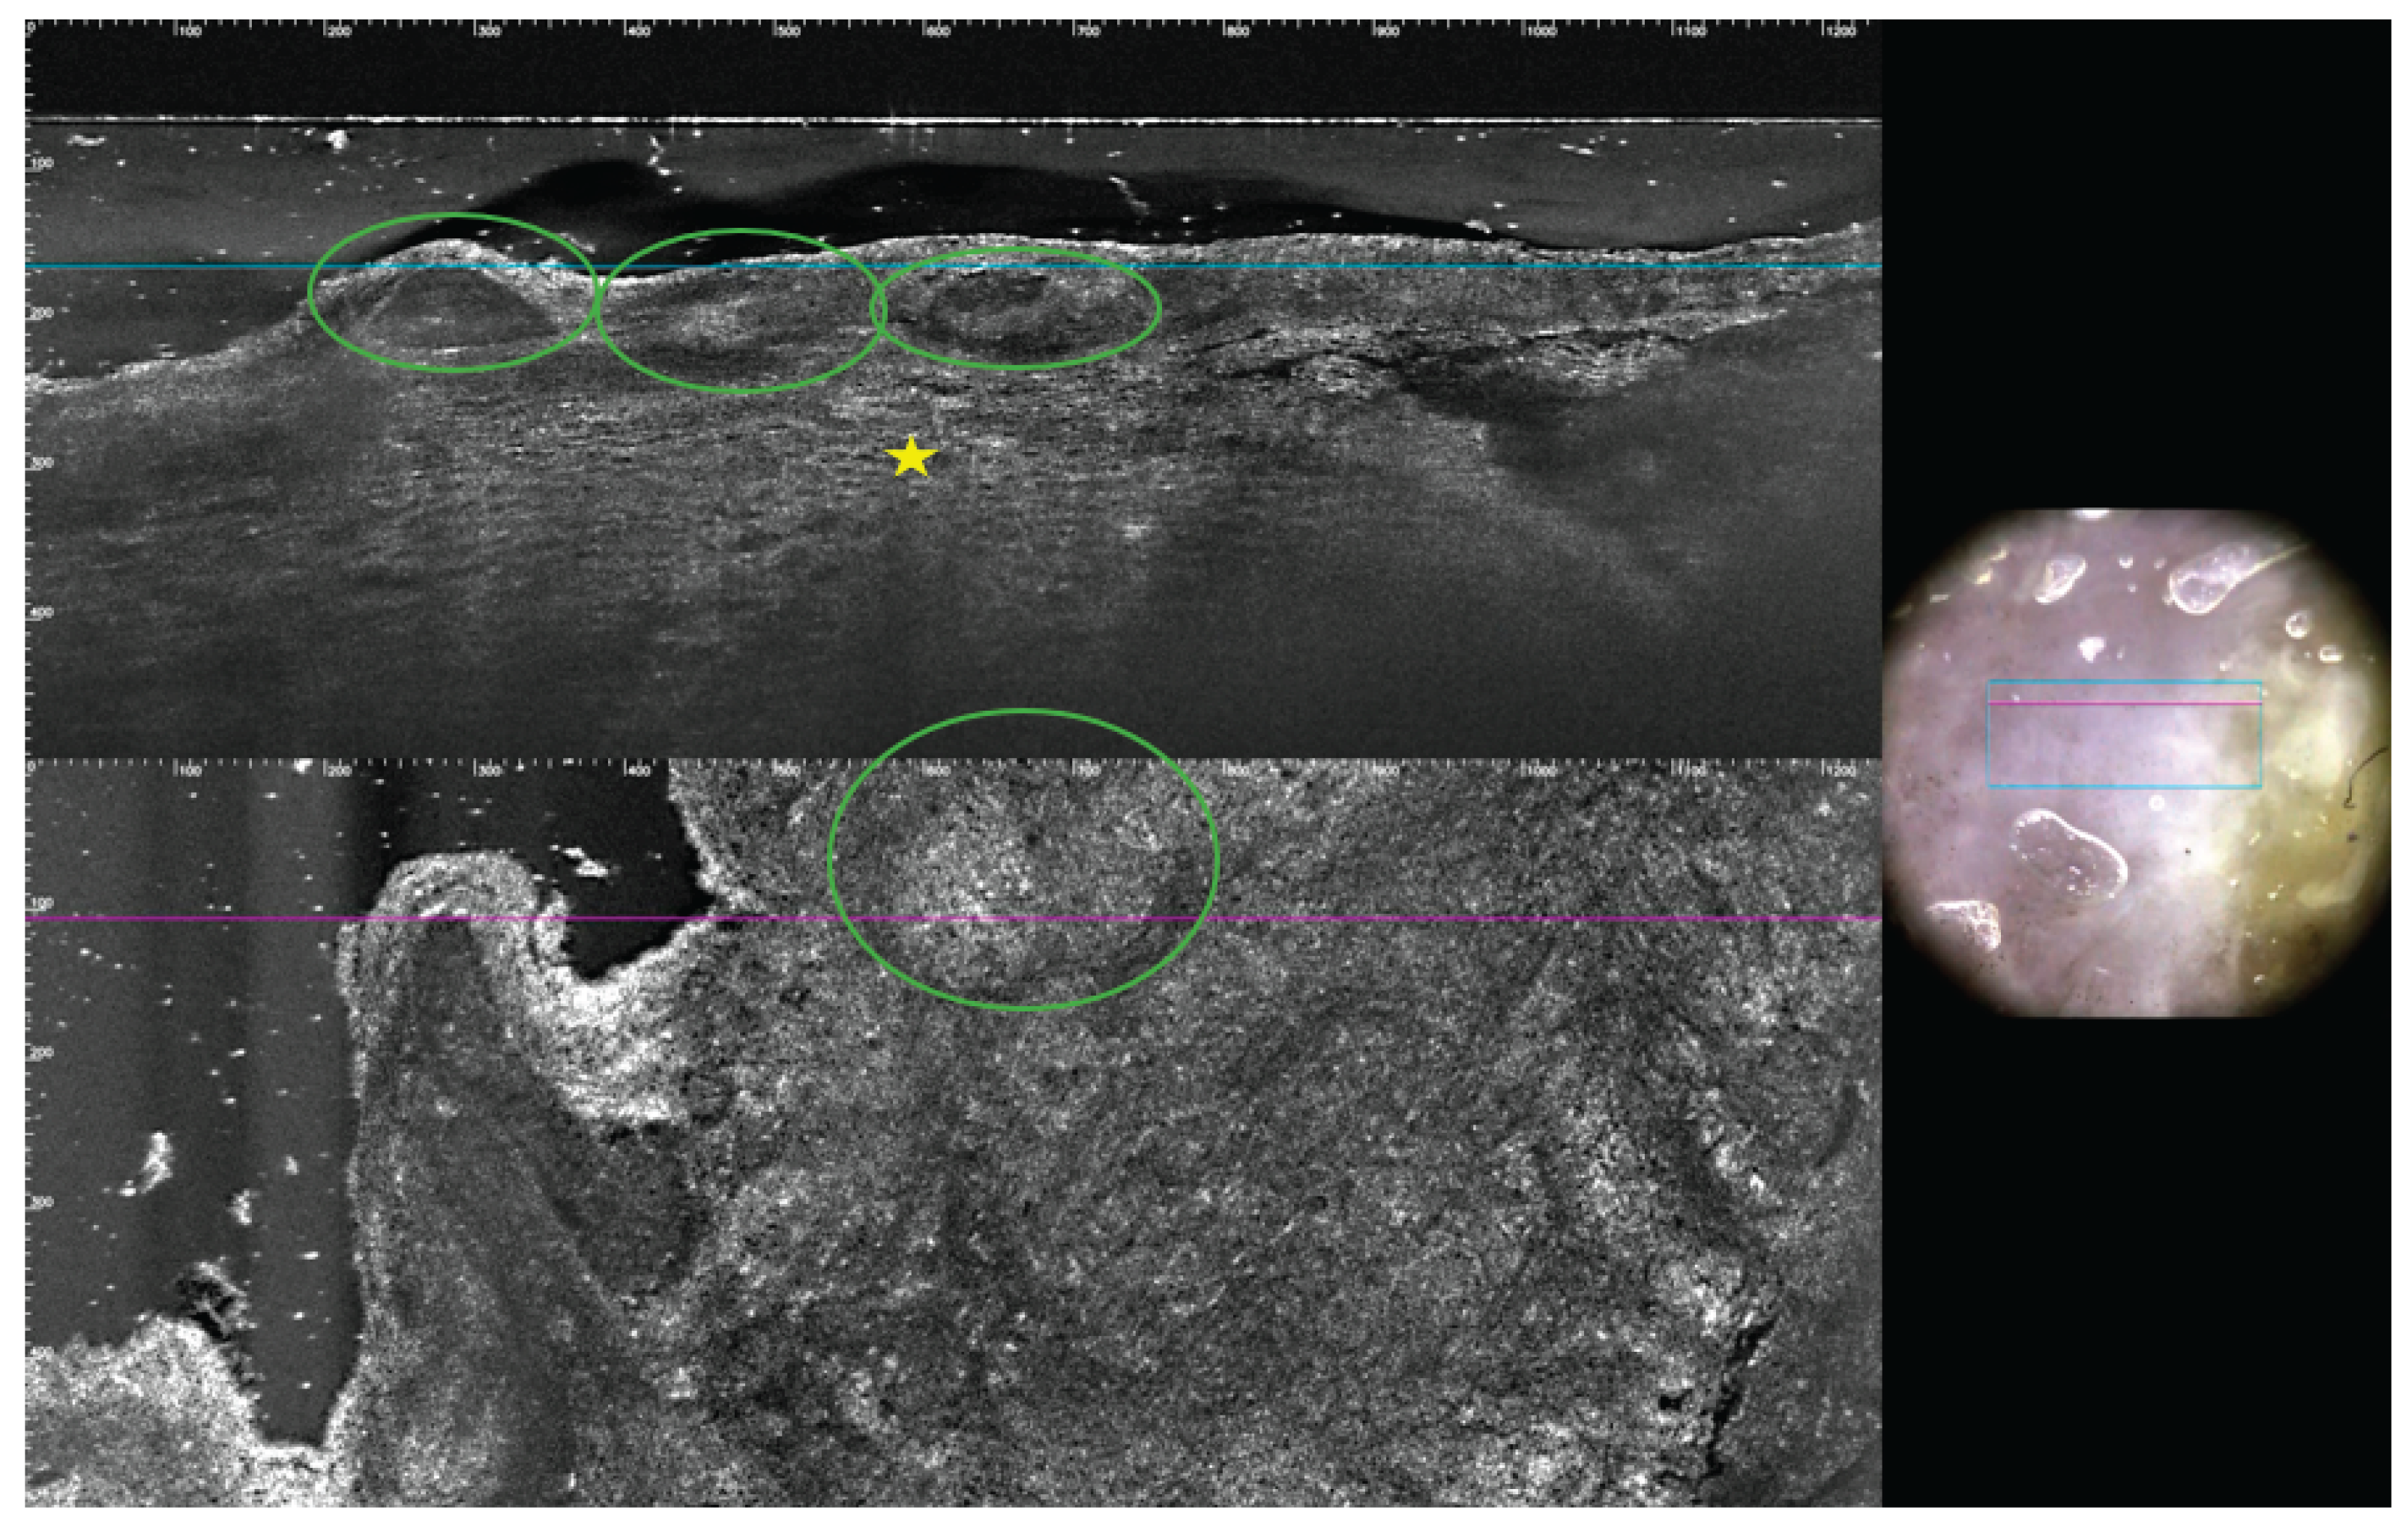

Figure 4.

LC-OCT is a innovative non-invasive imaging technique that uses light to capture high-resolution cross-sectional images of tissues [

12]: in this patient, LC-OCT examination demonstrated the presence of pseudovescicular pattern (green circles) altering normal epidermal architecture, full of atypical cells (yellow star) with mildly bright nuclei and several atypical cell nests, even in the dermis, at transversal evaluation. After this non-invasive examination, it became evident that the patient was not affected by nipple eczema, which typically presents with intraepidermal vesicles (spongiotic pattern) filled with inflammatory cells and keratinocytes [